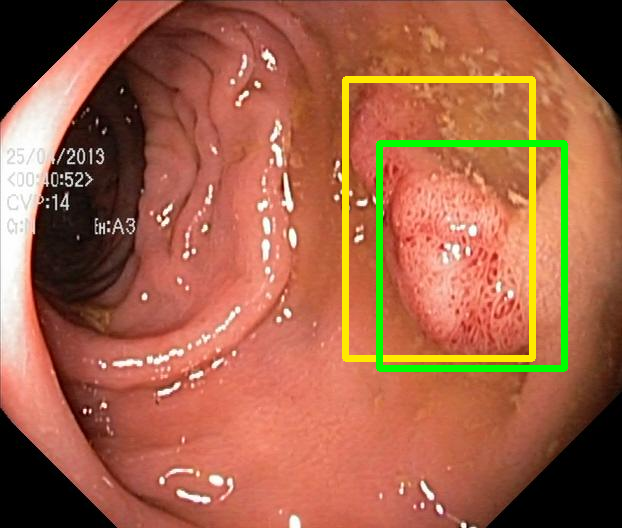

We evaluate the resulting object detection models using the test data, which is pre-processed in the same manner as the validation data, with AP@[.5:.95] (AP for conciseness), AP@.5 (AP5050{}_{50}start_FLOATSUBSCRIPT 50 end_FLOATSUBSCRIPT), and AP@.75 (AP7575{}_{75}start_FLOATSUBSCRIPT 75 end_FLOATSUBSCRIPT) computed for predicted bounded boxes with a confidence score \geq0.05. For all metrics, a higher value indicates better performance. The results are presented in Table VI, and some examples for predicted bounding boxes with a confidence score \geq0.5 are shown in Fig. 1.

RN-HK-MC RN-HK-BT RN-IN-MC RN-IN-BT RN-IN-SL RN-NA-NA Refer to caption Refer to caption Refer to caption Refer to caption Refer to caption Refer to caption Refer to caption Refer to caption Refer to caption Refer to caption Refer to caption Refer to caption VT-HK-MC VT-HK-MA VT-IN-MC VT-IN-MA VT-IN-SL VT-NA-NA Refer to caption Refer to caption Refer to caption Refer to caption Refer to caption Refer to caption Refer to caption Refer to caption Refer to caption Refer to caption Refer to caption Refer to caption

Figure 1: Targets (yellow bounding boxes) and predictions (green bounding boxes) for two randomly selected instances of the Kvasir-SEG test set. For conciseness, we denote ResNet50s with RN, ViT-Bs with VT, Hyperkvasir-unlabelled with HK, ImageNet-1k with IN, MoCo v3 with MC, Barlow Twins with BT, MAE with MA, supervised pretraining with SL, and no pretraining with NA-NA.